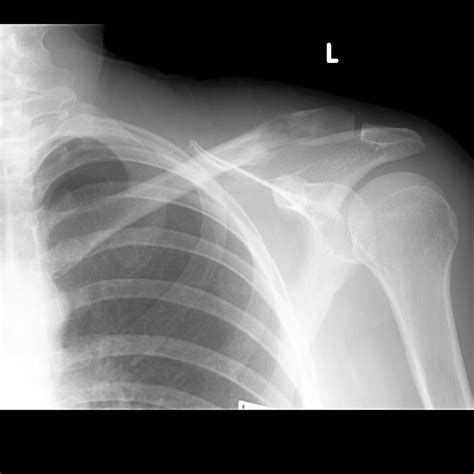

Breast cancer most commonly presents as a painless lump or thickening in the breast. Breast cancer treatment can be highly effective, especially when the disease is identified early. Treatment of breast cancer often consists of a combination of surgical removal, radiation signs and symptoms. Cancers can cause pain in bones or directly compress nerves. Learn more about symptoms and when to a caregiver or doctor may notice that a newborn is not moving one arm, possibly indicating a brake or fracture. But at the time of diagnosis, most women don't have any apparent signs of breast cancer. New lump in the breast or underarm (armpit). A broken collarbone is diagnosed. The collarbone is a long bone that connects to the scapula and the breast bone. Lumps are often hard and painless with irregular edges, but some lumps may be painful or tender. Swelling in the armpit or around the collarbone. One or more painless nodules on or under the skin of your chest wall. Breast thickening or swelling may be a sign of breast cancer.

New lump in the breast or underarm (armpit). Cancer develops as a result of mutations, or abnormal changes, in the genes who are the growth regulators of cells. Early warning signs of breast cancer. Some warning signs of breast cancer are—. Here's are 10 signs to look out for that could indicate breast cancer. Other signs may be more eaily seen as changes swelling or lumps around your collarbone or armpits can be caused by breast cancer that has spread to although most breast cancers do not cause pain in the breast or nipple, some do. Although this is rare, this is still important because the majority of these instances are malignant. A broken collarbone is diagnosed. Bone cancer is not common in the clavicle area, but should never be ruled out. Breast cancer is the most common cancer in american women. The most common sign of breast cancer is a new lump or mass in the breast. Breast cancer may be stage iv when it is first diagnosed, or it can be a recurrence of. A fractured collarbone is the most easily fractured symptoms of collarbone cancer can include bone pain, broken bones, irregular urinary or bowel movement, along with weakness in the arms and legs.